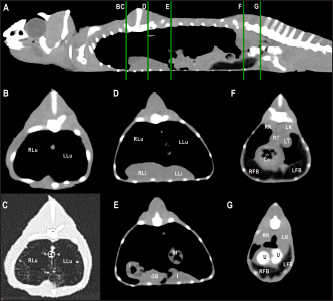

Fig. 2. Sagittal precontrast CT images displayed in soft tissue window (A and F) with length and height measurements of heart, liver, gallbladder, testes, kidneys, and fat bodies in a veiled chameleon (C. calyptratus). The precontrast CT transverse images displayed in soft tissue windows B–E show the width and height measurements of the same organs. H, heart; RLi, right liver lobe; LLi, left liver lobe; GB, gallbladder; RK, right kidney; LK, left kidney; RT, right testicle; LT, left testicle; RFB, right fat body; and LFB, left fat body.

The CT examinations were performed with a 16-slice helical CT scanner (General Electric Brivo CT 385) in cranio-caudal direction with the animals positioned in ventral recumbency (Fig. 1). All studies were obtained with a slice thickness of 0.625 mm, interval thickness of 0.625 mm, collimation pitch of 0.5625:1, 120 kV, 80 mA, field of view of 20 cm and a matrix of 512 × 512. The transverse images were reconstructed in sagittal and dorsal planes using multiplanar reconstruction. CT images were displayed in a soft tissue window (window level: 350; window width: 40) and a lung window (window level: −500; window width: 1,500). Coelomic organs height and width were assessed on the transverse images and length was assessed on the sagittal and dorsal reconstructions (Fig. 2).

Fig. 8. Sagittal precontrast CT image displayed in soft tissue window (A) and selected corresponding transverse images represented as green line section, displayed in soft tissue window at the level of the liver (B), ovaries (C), and kidneys/fat bodies (D) in a female panther chameleon (F. pardalis). E, eggs; RLi, right liver lobe; LLi, left liver lobe; ROv, right ovary; LOv, left ovary; RK, right kidney; LK, left kidney; LFB, left fat body.